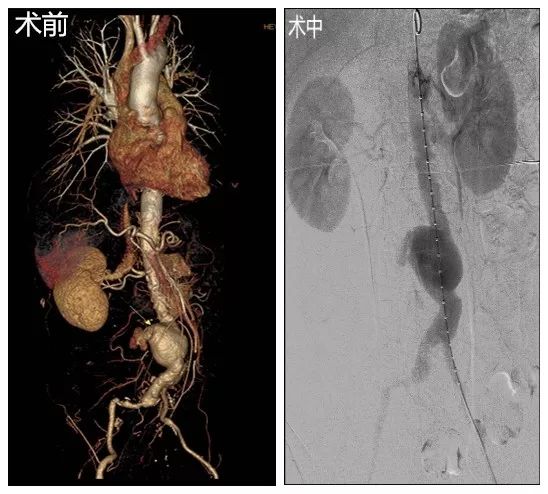

患者张某,69岁,腹痛5小时急诊入院,查体:心率120次/分,血压70/55mmHg贫血貌,腹部膨隆,腹肌紧张,全腹压痛,双下肢足背动脉搏动减弱,主动脉CTA提示:腹主动脉瘤右侧壁破裂并右侧腹膜后区-右肾周间隙血肿、骶前间隙积血,腹主动脉中下段-双侧髂总动脉动脉瘤并血栓形成。明确诊断后,立即送至我科,与家属交代病情取得理解后,麻醉、导管室、输血科、ICU等相关科室做好准备后,介入血管心脏外科李立涛副主任医师带领手术团队着手为该病人进行手术。克服患者血压低,左侧髂外动脉重度狭窄并短段闭塞,导管不能通过闭塞处的不利因素,李立涛副主任医师在团体的帮助下,依次予以覆膜支架隔绝破裂的腹主动脉瘤,放置1个支架主体及3个分支支架,造影见腹主动脉瘤被隔绝,未见显影,无内漏,双肾动脉及髂动脉显影良好,血流速度可,术后转ICU继续治疗,经过ICU悉心治疗后,术后1周复查主动脉CTA,动脉瘤隔绝良好,支架位置准确,患者康复出院。